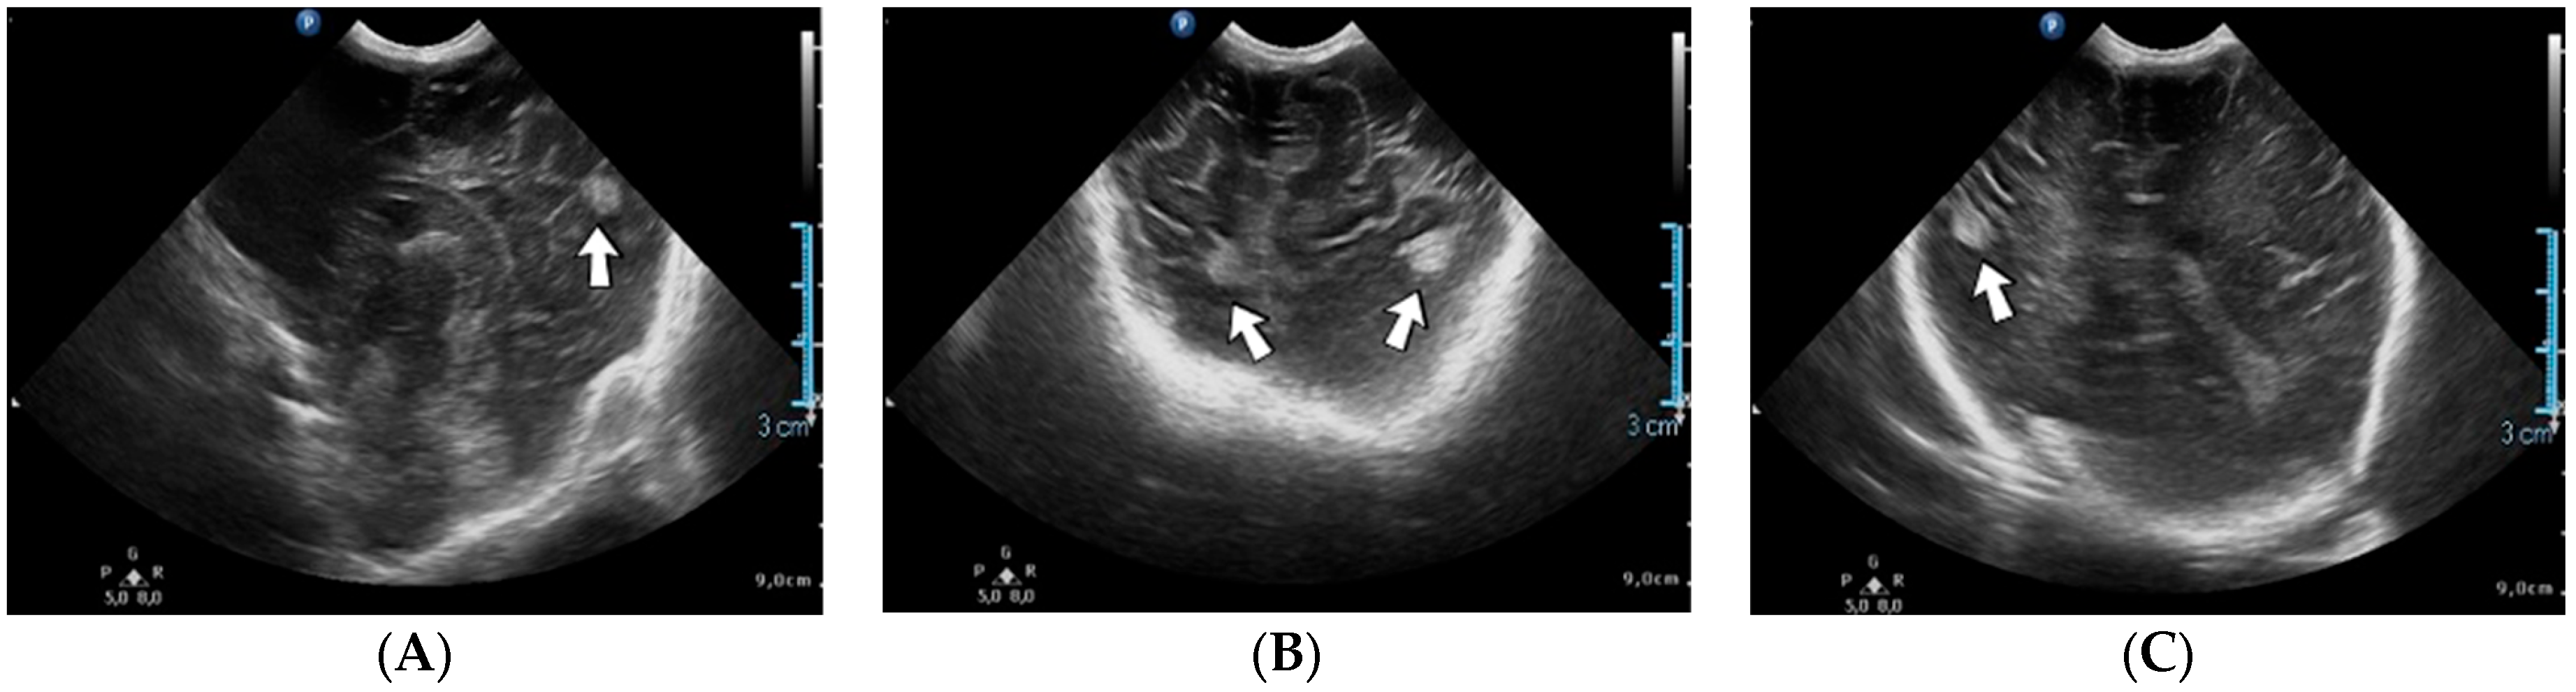

A 19-day-old male neonate (35–36 weeks, 2.20 kg) presented with thrombosis of the right pulmonary artery diagnosed on the same day at another pediatric emergency department, where treatment with continuous heparin infusion was initiated. The admission laboratory findings showed elevated c-reactive protein, modified coagulation tests (ongoing anticoagulation treatment), and elevated D-dimer tests. The cardiac ultrasound identified thrombi in the right atrium and ventricle (Figure 15). Therapy with heparin was continued, to which alteplase was added. After four days of anticoagulation and fibrinolytic therapy, the thrombi could no longer be noticed on ultrasound or CT scan.

Figure 15.

Intracardiac thrombosis was identified on cardiac ultrasound: in the right pulmonary artery (A), the right atrium (B), and the right ventricle (C).

Genetic testing confirmed inherited thrombophilia, with a positive MTHFR C677T homozygous gene mutation and Antithrombin, Protein S, and Protein C deficiencies. A mild elevation of PAI-1 levels was detected. There was limited information about the family history.

4.36. Case No. 36—Postnatal Intracardiac Thrombosis

A 7-week-old male infant (36 weeks, 2.50 kg), the first twin from a twin pregnancy, presented with a complex congenital cardiac malformation for an elective surgical procedure (Blalock–Taussig shunt). Heparin infusion for the shunt was started immediately after the intervention and anticoagulation was continued with enoxaparin due to good clinical condition. Then, 18 days after the procedure, a routine cardiovascular ultrasound revealed a thrombus in the left ventricle (Figure 16). The laboratory studies showed leukocytosis, highly elevated c-reactive protein, and modified coagulation tests (due to anticoagulant treatment). Continuous heparin infusion was reinitiated, but multiple intracardiac thrombi were detected during the following days. Treatment with alteplase was also started, but the patient’s condition continued deteriorating, leading to a negative outcome due to cardiac failure.

Figure 16.

Intracardiac thrombosis identified on cardiac ultrasound: left atrium and ventricle (A), left ventricle (B), apex (C).

Genetic testing confirmed inherited thrombophilia, with positive PAI-1 4G/5G promoter, MTHFR A1298C homozygous gene mutations, and Antithrombin and Protein C deficiencies. There was no known family history of thrombophilia. The mother had a previous therapeutic abortion due to a prenatal diagnosis of a complex congenital cardiac malformation.